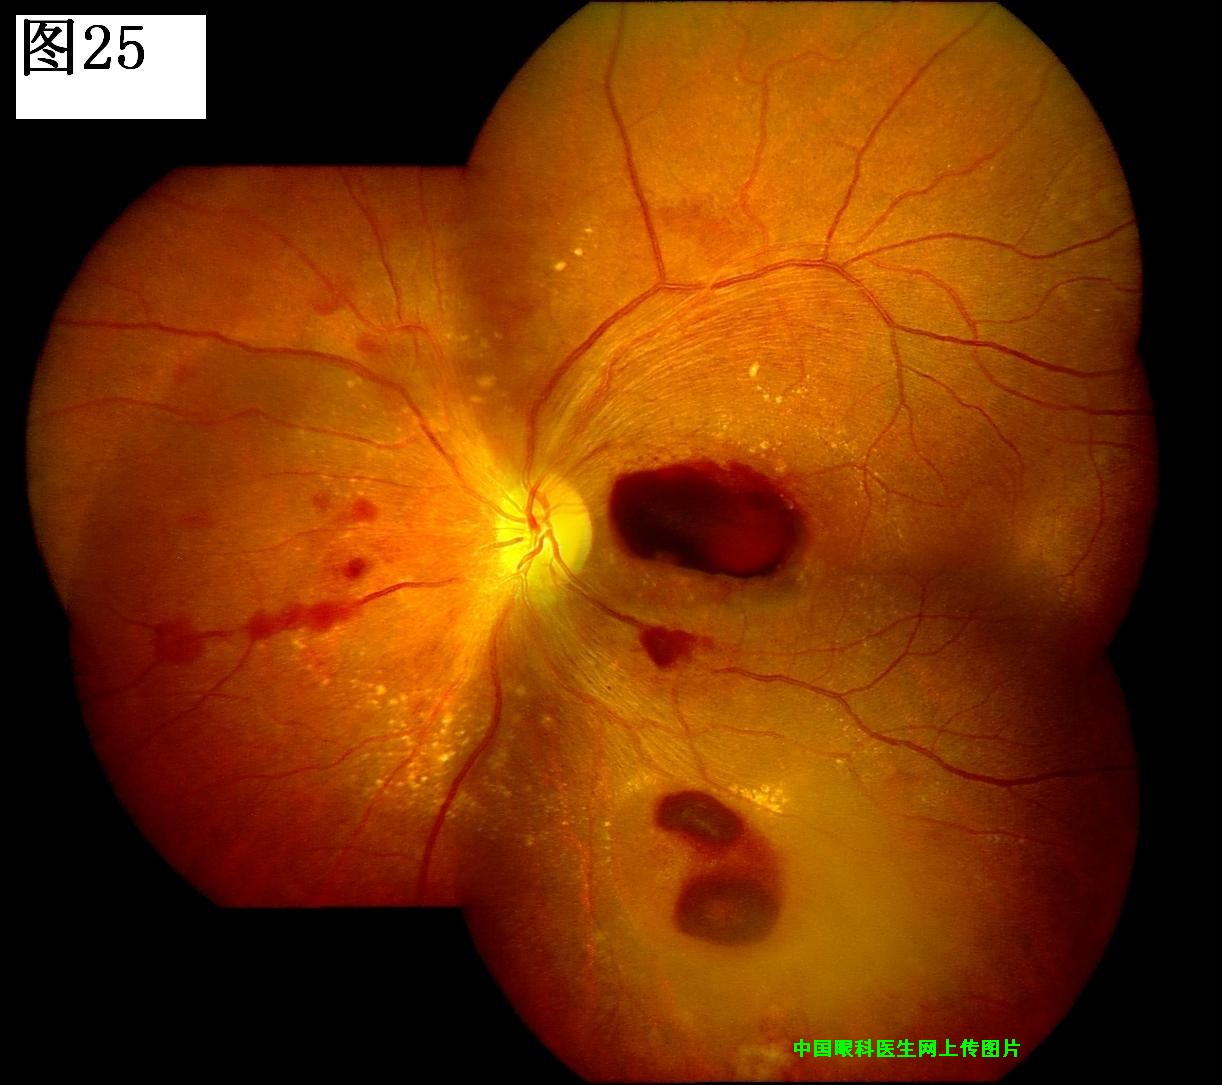

优秀眼底图片奖应征作品展示

25 26 27 28